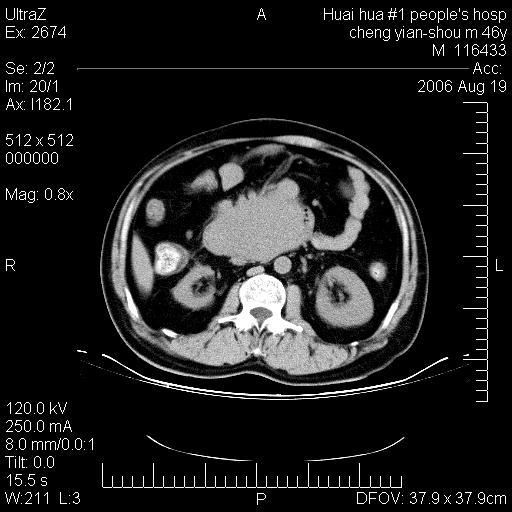

患者,男,46y。腹痛2月,消瘦。

十二指肠水平段占位,考虑间质瘤或平滑肌瘤。

肿块较大,腹膜后占位,境界欠清,周边脂肪密度较高呈条状影,有没有脂肪肉瘤可能,

缺少完整的三期图像。考虑肠系膜脂膜炎mp(肿块型)。

鉴别:间质瘤(这么大而无囊变不可思议)、平滑肌瘤/肉瘤、淋巴瘤、类癌,脂肪类肿瘤、转移瘤等。

十二指肠水平段占位,考虑间质瘤。

首先考虑小肠间质瘤。

十二指肠水平段软组织密度占位,考虑间质瘤可能性大。

腹膜后占位,境界欠清,考虑来源于十二指肠病变,间质瘤或平滑肌肉瘤可能性大。建议活检。

手术病理结果:原发性小肠恶性淋巴瘤(primary gastrointestinal lymphoma,pgil)是原发于胃肠的淋巴网织系统的恶性肿瘤,在结外淋巴瘤中居第一位,该病少见,临床无特异性,诊断困难,术前主要依靠影像学诊断。胃肠道本身具有较丰富的淋巴组织,因而胃肠原发性淋巴瘤是结外淋巴瘤最常见的部位,文献报道约占胃肠道恶性肿瘤的1%~4%,其中胃约占50%~70%,小肠约占35%~70%,结肠约占4%~6%。影像检查在pgil的诊断及分期中有重要的作用,ct是很有价值的检查方法。

胃肠淋巴瘤病理特点:胃肠道原发性淋巴瘤起源于胃肠壁固有层和黏膜下层的淋巴组织即胃肠粘膜相关淋巴组织(malt),多为粘膜相关淋巴瘤。病理上通常为非霍奇金淋巴瘤,且决大多数来源于b淋巴细胞,很少见于霍奇金淋巴瘤。胃肠原发淋巴瘤比胃肠道癌的发病率要低的多,最常见于胃,其病因可能跟幽门螺杆菌感染有关。幽门螺杆菌能引起胃粘膜损害,引起炎性及免疫反应,淋巴细胞聚集并形成滤泡,可影响胃的正常生理功能,导致胃淋巴瘤的发生。单纯性小肠淋巴瘤是常见好发于回盲末端,受累的肠段较长,可单发、多发,甚至累及整个小肠。原发性大肠淋巴瘤罕见,以直肠和盲肠最多见。病变大体观可表现为胃肠腔内外的肿块,也可表现为从黏膜下到浆膜面肠壁的纵向浸润,并且常常伴有肠系膜淋巴结肿大。任何情况下,肿瘤几乎总是导致一定程度的肠壁增厚,可对称或不对称,病变与正常组织间常无明确分界,肠腔可狭窄、正常或动脉瘤样扩张,后者主要是肿瘤在肠壁内浸润,破坏肠壁内植物神经丛所致。以上改变成为ct检测病变的病理基础。

肠道淋巴瘤的ct表现分为4类

1) 壁内浸润型, (2)多发结节型, (3)肠系膜受累伴腔外肿块型(本型就是),(4)肿块型。